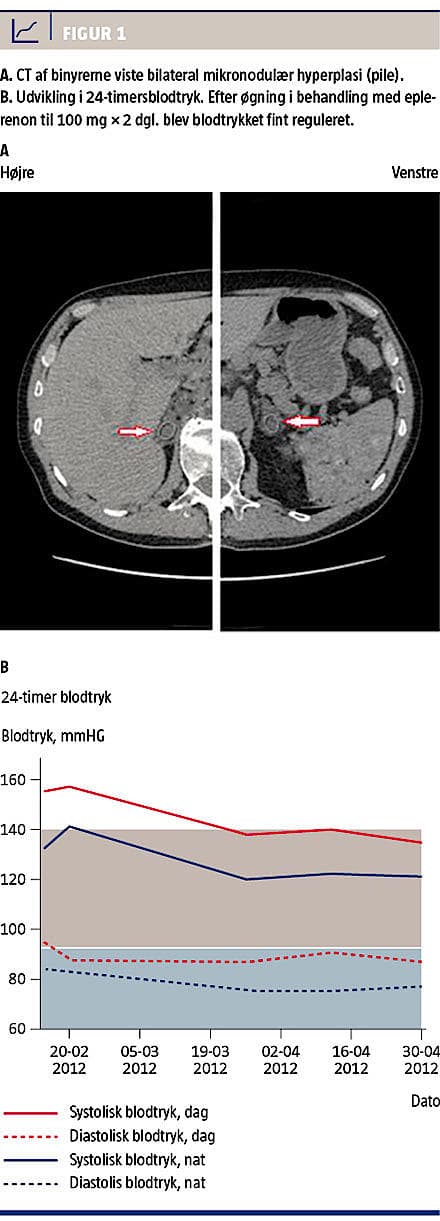

3,2 mmol/l. Der var normale værdier af følgende: P-kreatinin (90-100 mikromol/l), captopril renografi, P-metanefrin samt urinudskillelse af noradrenalin og adrenalin. Urinalbuminniveauet blev målt til 83 mg/l. En CT af binyrerne viste bilateral mikronodulær hyperplasi (Figur 1A). P-reninniveauet var lavt (0,2 ng/ml/t. i hvile og 0,16 ng/ml/t. efter aktivitet) og P-al-

efter at patienten havde været oppe i 4 t. både før og efter (NaCl steg fra 2.735 til 3.508 pmol/l og P-renin fra 0,04 til 0,13 ng/ml/t.). Efter øgning i behandling med aldosteronantagonisten eplerenon til 100 mg × 2 dgl. blev BT fint reguleret (Figur 1B), og hovedpinen forsvandt. Der var fortsat tendens til svingende P-kaliumniveau, men det steg helt op til 3,8 mmol/l.